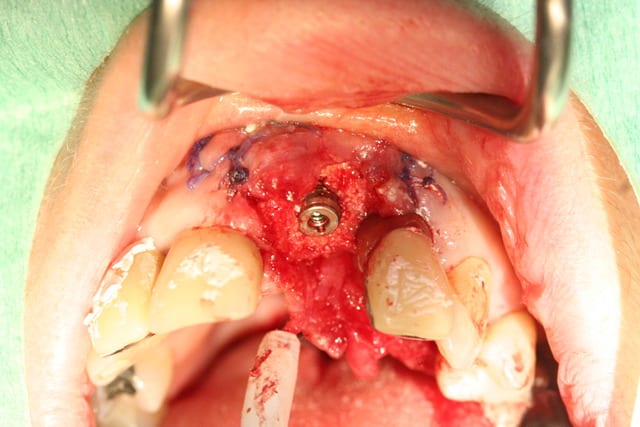

Le cas EII sur 12

positionnement de l'implant en ménageant un espace en vestibulaire qui st comblé avec de l'os synthétique car l'espace est important et il y a une perforation de la corticale vestibulaire en regard de l'apex de la dent.

pour recouvrir tout cela et gagner un peu de volume vestibulaire

un lambeau palatin pédiculé qui après une rotation va recouvrir l'implant et la greffe.